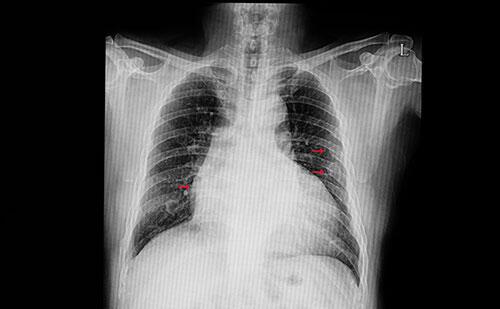

Büyük risk altındayız! Ölümler en çok bu hastalıktan oluyor...

Son verilere göre 2030 yılında dünya genelinde 23 milyon kişinin kalp kaynaklı hastalıklardan hayatını kaybedeceği tahmin ediliyor. Ancak ciddi kalp hastalıklarının önemli bir çoğunluğu risk faktörlerinin kontrol altına alınabilmesi sayesinde önlenebiliyor.

Hayat boyu hiç mola vermeden çalışmaya devam eden kalp arada yorulup görevini aksatabilmektedir. Sağlıksız beslenme, sigara, stres, hareketsiz yaşam kalp ve damar hastalıklarına sebep olan faktörler arasında yer alırken; bu faktörlerin kontrol altına alınması ve vücudu dikkatli izlemek hayat kurtarıcı olabilmektedir. Bazen genç yaştaki kişiler kalp hastalığından endişe etmek için çok erken olduğunu düşünüp, dikkatsiz davranabilmektedir. Oysa erken yaşlarda atardamarlarda plak oluşumu başlayabilmektedir. Ailede kalp hastalığı, diyabet gibi hastalıklar da varsa; genç kişi fazla kilo sahibiyse damarlar bundan erken yaşta ve olumsuz etkilenebilmektedir. Damar sertliğine bağlı koroner arter hastalığında genetik etkenlerin yanında sağlıksız yaşam alışkanlıklarının da etkili olduğu bilinmektedir.